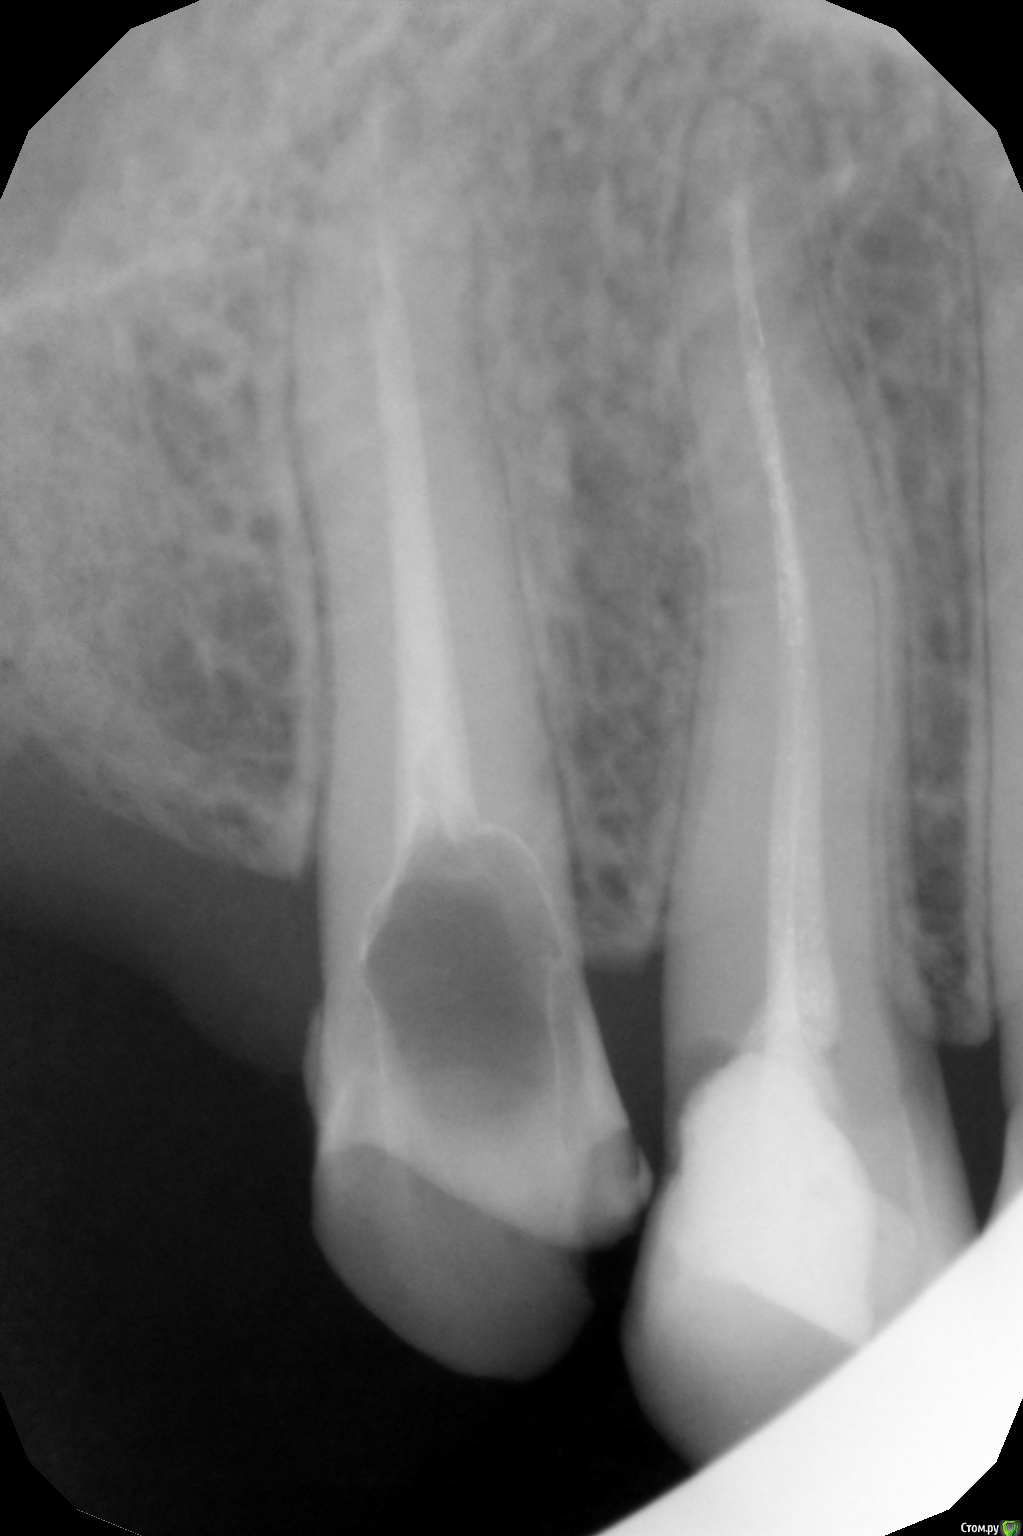

Musya31 Опубликовано 14 октября, 2016 Автор Поделиться Опубликовано 14 октября, 2016 (изменено) Была, конечно. Рекомендация 1 - протезироваться, а там смотреть как сустав себя поведет. 2.- делать расслабляющую шину, смотреть на эффект, решать дальше насчет капы, потом протезироваться. Т.е. два диаметрально противоположных мнения. Снимки свежие. Просто орто незадолго до удаления, прицельный через 2 недели после удаления. Вот еще свежий 5-ка которая тоже ужасно болит. А с какими еще зубами проблема? Изменено 14 октября, 2016 пользователем Musya31 Ссылка на комментарий

annda Опубликовано 20 октября, 2016 Поделиться Опубликовано 20 октября, 2016 (изменено) У вас не зубы болят, у вас миофасциальные боли, либо нейропатия. Нужен нейростоматолог или невролог.Иногда , когда анальгетики не помогают, применяют препараты ботокса в жевательные мышцы.Это уже когда совсем край. Найдите врачей, практикующих этот метод. В Москве они должны быть.5 ку свою вы просто раздавливаете своим бруксизмом( или клинчерством), скорее всего по ночам, а возможно и днем зубы стискиваете,там на снимке видно пародонт неспокойный. Она одна стоит, опираться ей не на кого, вот и не выдерживает, больно связке. Пусть пока просто пришлифуют чуть- чуть или каппу делайте. Изменено 20 октября, 2016 пользователем annda Ссылка на комментарий